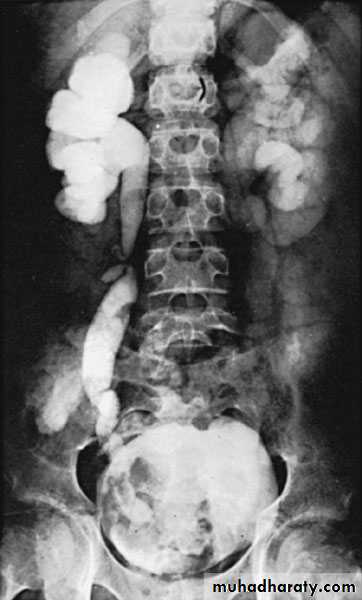

U/S: pus collection around the kidney with or without hydronephrosis.

KUB: obscured psoas shadow, spine scoliosis,.

Drinage of perinephric abscess